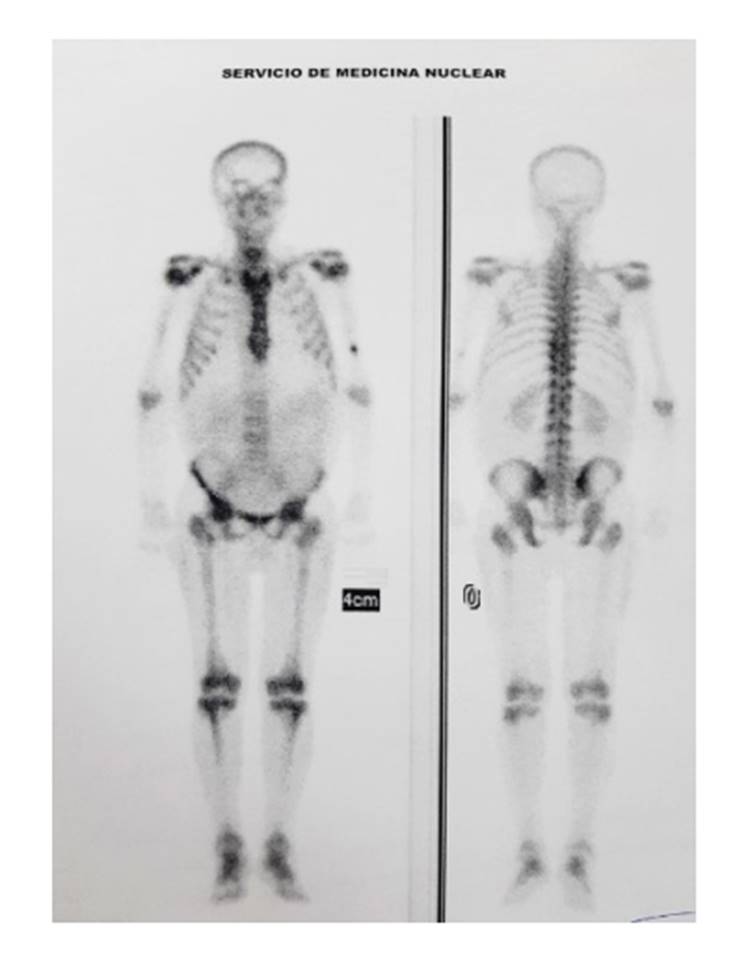

En las pruebas de laboratorio se encontró un hipotiroidismo primario, endocrinopatía e hipogonadismo primario (Tabla 1); y el ultrasonograma testicular, hidrocele con predominio en el lado derecho. El estudio de la electromiografía por parestesias fue compatible con polineuropatía sensitiva motora axonal severa en miembros inferiores (Figura 2). Por último, la gammagrafía ósea mostró hipercaptación del radiofármaco a nivel de articulaciones de la rodilla, tibioperonea astragalina y coxofemoral en relación a procesos inflamatorios (Figura 3).

Figura 3 La gammagrafía ósea muestra hipercaptación del radiofármaco en las articulaciones de rodilla, tibioperonea astragalina y coxofemoral relacionada a procesos inflamatorios